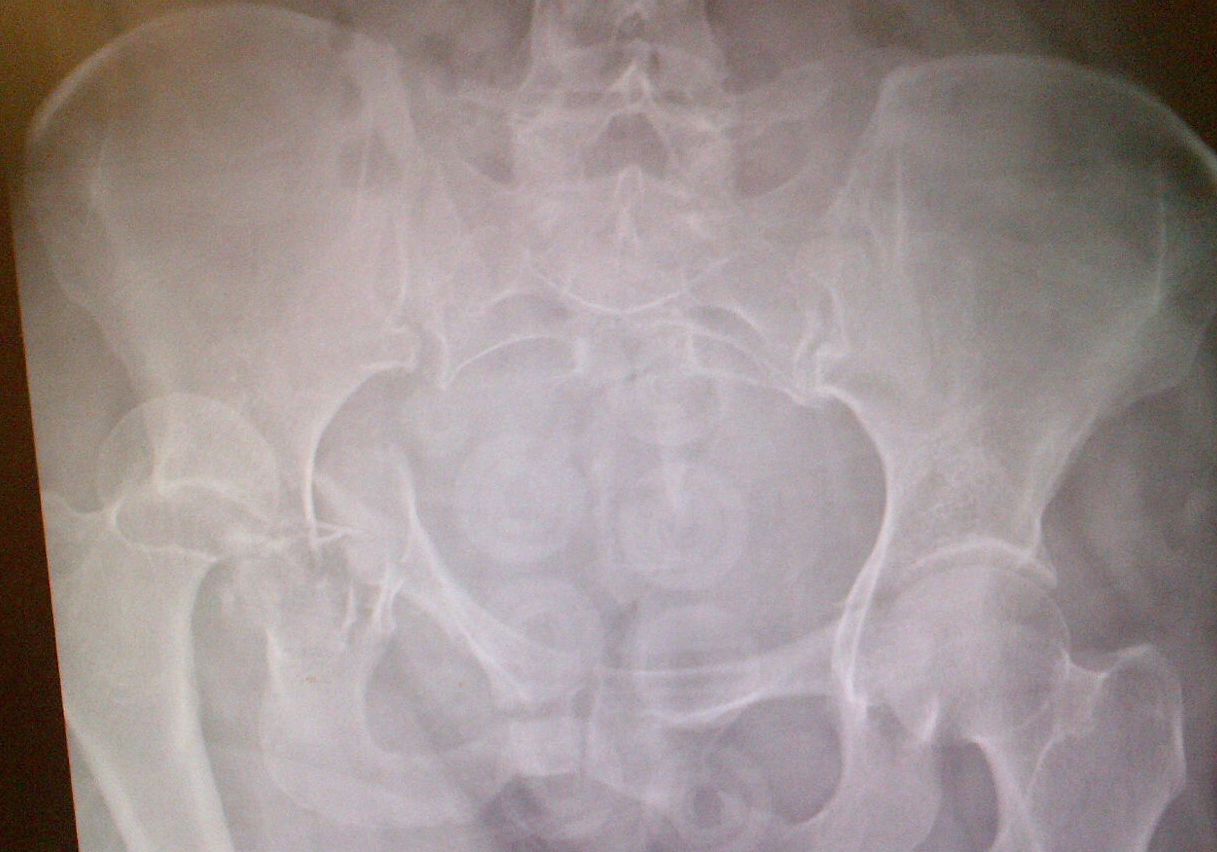

Clinical Features / Xray

Posterior dislocation

- leg shortened, flexed, adducted & internally rotated

- head small on xray

Anterior dislocation

- leg short and externally rotated

- head larger on xray

Check NV status / sciatic nerve

Non-concentric Reduction

Esssential to obtain X-ray and CT after reduction

X-ray

- head - teardrop distance must equal contralateral side